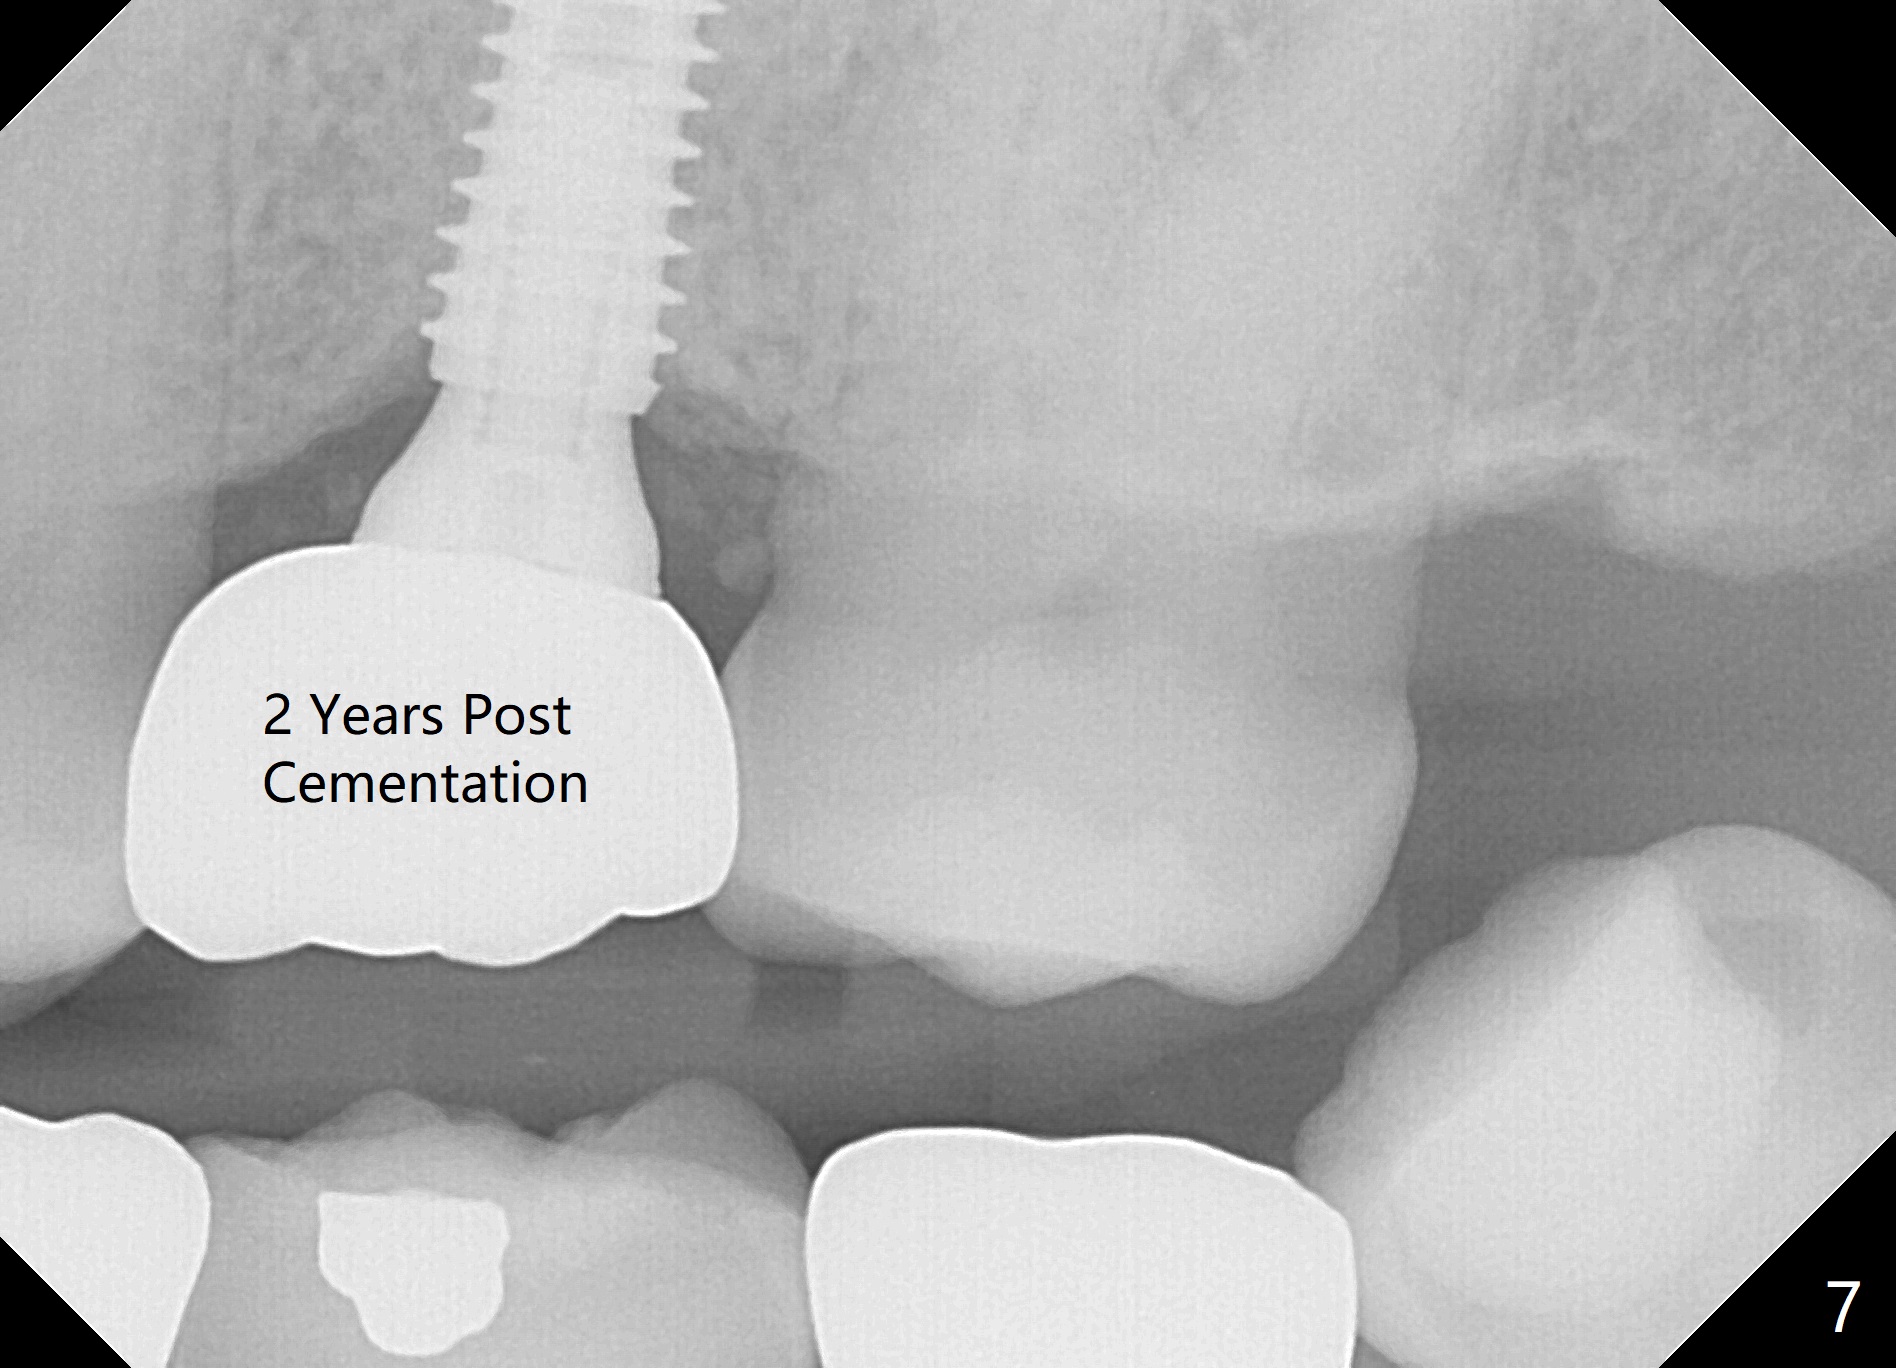

The edentulous area at #14 is moderately atrophic, After incision, the bone is too hard for #15 blade for bone expansion. Osteotomy is initiated with 1.2 mm drill, followed by insertion 1.3/2.3 mm bone expander (Fig.1). Use the same instruments are reused twice to change the trajectory (Fig.2,3). Finally Lindamann bur is utilized to move the osteotomy distally by ~ 2 mm; bone expansion continues until 2.4/3.7 mm expander for 13 mm with 50 Ncm (Fig.4). The last expander 3/4.4 mm barely enters the osteotomy for 6 mm. A 3.7 mm drill has to be used for 12 mm before placement of a 4.5x11.5 mm implant with >35 Ncm (Fig.5). A 5.5x5(3) mm abutment is placed with allograft (<) placed around the implant. Following suturing, periodontal dressing is applied around the implant. The abutment dislodges 3 months postop (Fig.6). Crown is delivered 3 weeks later. The abutment screw is retightened ~ 2 months later. He is a bruxer. The abutment screw is loose again <2 years post cementation (6 months post #18 screw retightenting and occlusal reduction), probably related to distal implant placement (Fig.7).